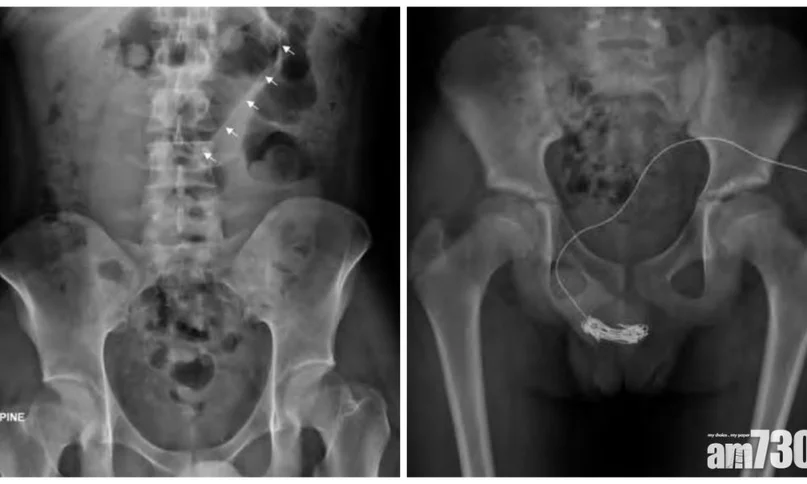

男童及母親曾嘗試取出電線但不成功,母親於是帶男童到醫院求助,照X光片檢查,顯示陰莖尿道上纏有的電線長達20厘米,當中未包括糾纏的部分,無法以牽引方式取出電線,最終決定開刀切開陰莖中段的尿道,取走電線。男童術後兩天出院,需「孭尿袋」兩周才恢復。不過醫生指,需幫男童進行重建尿道手術,他日後或會出現尿道收窄等後遺症。